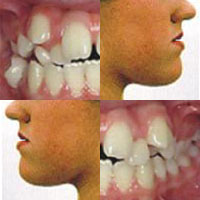

Στόχος της ορθοδοντικής θεραπείας είναι η αποκατάσταση της ανώμαλης σχέσης μεταξύ των γνάθων και των δοντιών, καθώς και των δυσμορφιών του προσώπου που πιθανόν να συνεπάγονται από τα προβλήματα. Πραγματοποιείται μέσω της μετακίνησης των δοντιών σε μια νέα επιθυμητή θέση με άσκηση συστημάτων δυνάμεων στα δόντια ή/και στα οστά μέσω των ορθοδοντικών ή/και ορθοπεδικών συσκευών.

Η Ορθοδοντική προλαμβάνει, διαγιγνώσκει και θεραπεύει τα ορθοδοντικά προβλήματα για λειτουργικούς και αισθητικούς λόγους. Παίζει σημαντικό ρόλο στη βελτίωση της στοματικής υγείας, εξασφαλίζει αρμονία μεταξύ δοντιών και προσώπου και χαρίζει ένα όμορφο και λαμπερό χαμόγελο, το οποίο βελτιώνει τη ποιότητα ζωής μας σε προσωπικό και επαγγελματικό επίπεδο αυξάνοντας την αυτοπεποίθησή μας.